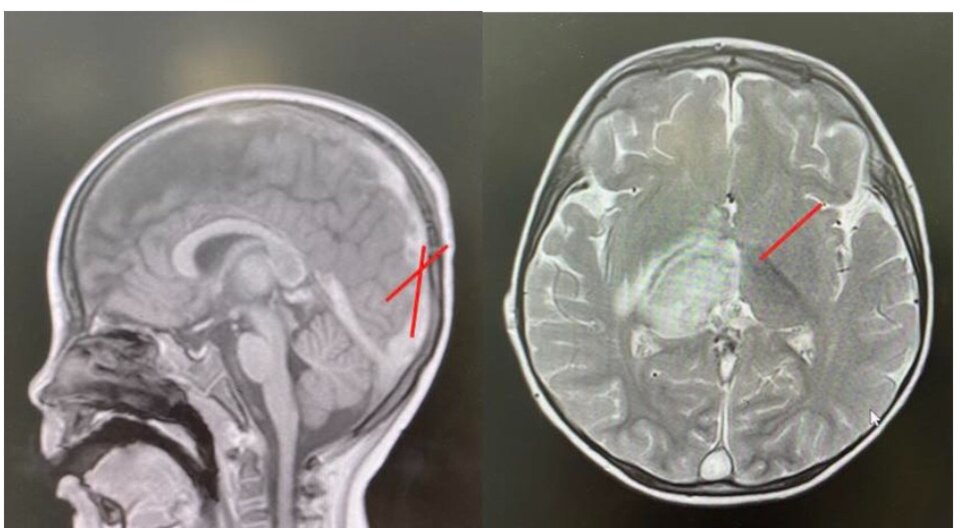

Hình ảnh huyết khối và tổn thương não của bệnh nhi trên phim chụp. Ảnh: BSCC.

Chụp CT scan sọ não cấp cứu ghi nhận nhồi máu đồi thị kèm phù não xung quanh, huyết khối lan tỏa tĩnh mạch vỏ não, xoang tĩnh mạch nội sọ, kéo dài đến tĩnh mạch cảnh chung trái, đường giữa lệch sang trái. Chụp MRI sọ não cũng ghi nhận hình ảnh nhồi máu. Xét nghiệm dịch não tủy bình thường.